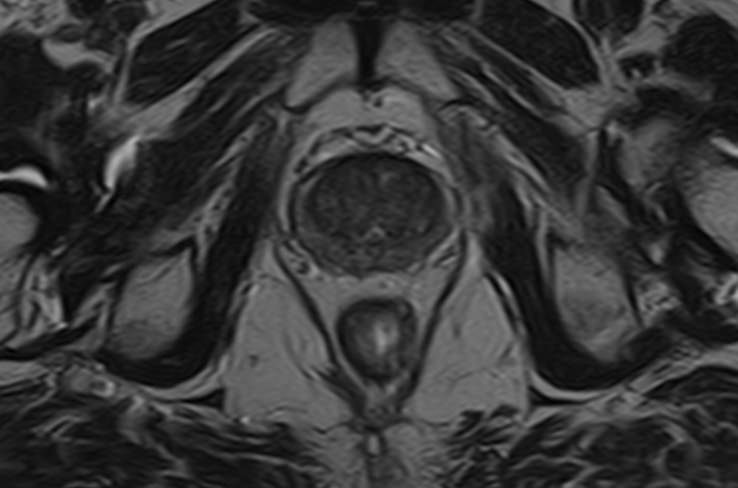

Простата расположена в труднодоступной для диагностики анатомической области, однако метод магнитно-резонансной томографии позволяет детально изучить структуру органа и окружающих ее тканей, включая семенные пузырьки (секреторные органы, вырабатывающие жидкую часть семенной жидкости) и семявыносящие протоки.

В клинике «Доступная медицина» диагностика заболеваний предстательной железы на экспертном уровне выполняется при помощи современного высокопольного магнитно-резонансного томографа TOSHIBA VANTAGE TITAN 1,5 Тесла. Аппарат производит сканирование в виде послойных тонких срезов с шагом от 1 мм и преобразует их при помощи новейших цифровых программ в изображения трехмерного формата. Методика позволяет получить максимально полную картину о состоянии структуры простаты и окружающих тканей и поставить точный диагноз.